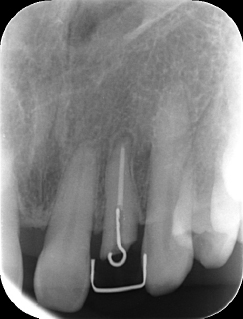

| 治療前で歯根が長いのがわかります。歯根がある程度長く無いと、MTMは行えません。 | MTM終了時のもの。フックが上の金属に接している。また根尖に透過像があるが、歯が動いた証拠です。 |

MTM治療開始時と終了後。右の根尖の透過像が実際に歯が動いた部分。